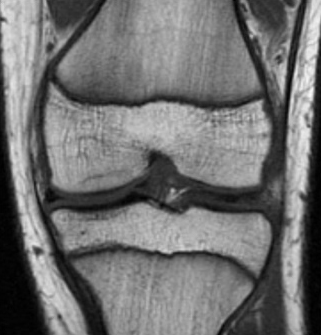

[Figure caption and citation for the preceding image starts]: Magnetic resonance imaging (MRI) of knee demonstrating healingFrom the collection of H. Chambers, MD [Citation ends].